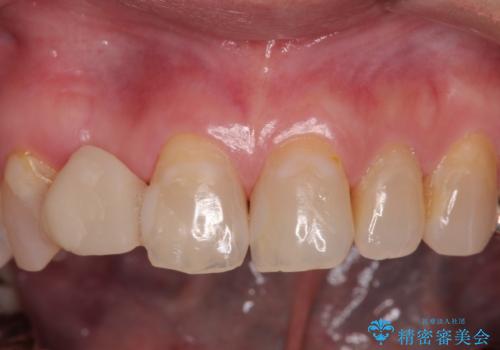

- 前歯のインプラント治療を検討して様々医院を探していたところ、1回の手術で治療ができるとのことで来院された患者様です。

長期間の治療と外科処置の回数が多くなることを懸念して、なかなかインプラント治療に乗り出せなかったそうですが、1DAYインプラントというものがあることを知り、当院にいらっしゃいました。

仮歯を事前に用意し、インプラント埋入時に即日で仮歯を装着する、即時荷重インプラントの計画で治療を進めて行くこととしました。